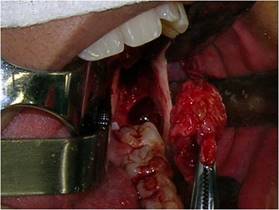

Bajo anestesia general, intubación nasotraqueal, tras antisepsia extra e intrabucal con solución de clorhexidina al 2 y al 0,12 %, respectivamente, se realizó la colocación del campo operatorio y el taponamiento del cruce orofaríngeo con "packing". Luego, se realizó una infiltración subperióstica a nivel de la región del trígono retromolar, donde había fluctuación por erosión cortical, con solución de clorhidrato de bupivacaína al 0,5 % con hemitartrato de epinefrina 1:200.000 para promover la hidrodisección perióstica y hemostasia. A continuación, se realizó la aspiración con una jeringa tipo luer de 10 cm³ con aguja 40X12 y se recolectó líquido seropurulento en cantidad abundante (Fig. 3).

En secuencia, se realizó una incisión circunferencial con un mango para bisturí n.º 3 equipado con una lámina 15, lo suficientemente profunda para penetrar al interior de la lesión. Además de extraer este tejido, también se extrajo un fragmento de la cápsula de la lesión por separado, con el fin de obtener una muestra más específica de la lesión (Fig. 4).

Todo el material extraído se fijó inmediatamente en una solución de formol al 10 %. Se realizó una sutura de puntos aislados en toda la zona resecada, abarcando la cápsula de la lesión y la mucosa circundante (Fig. 5). Después de la toilette de la cavidad con suero fisiológico, la cavidad restante se tamponó con una gasa con medicamento impregnada en sulfato de neomicina 5 mg/g y bacitracina zinc 250 UI pomada.

Inicialmente se extrajeron los elementos dentales 18, 28 y 48 mediante técnica quirúrgica tradicional. Luego, se abordó el quiste restante a través de una incisión elipsoide a aproximadamente 0,5 cm de la abertura del área de descompresión. Tras la enucleación total de la cápsula quística remanente y el elemento 38 (Fig.7), se realizó el taponamiento de la cavidad con gasa con medicamento impregnada de forma similar a la utilizada en la primera intervención (Fig.8).